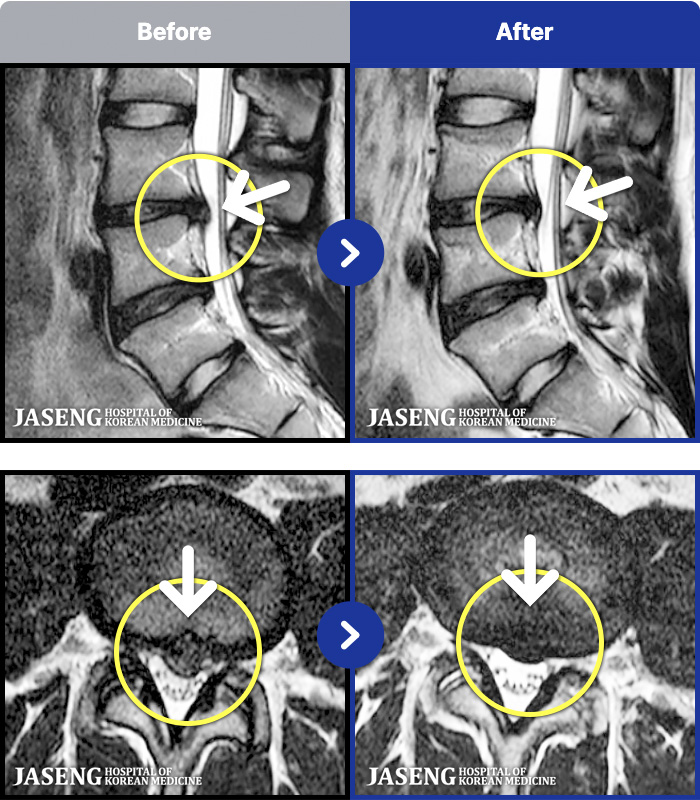

- MRI ġ

MRI ġ

191 MRI ũ ʸ Ȯϼ.

[Կñ:23.07.31~26.01.25]

[_㸮ũ] ϴ.